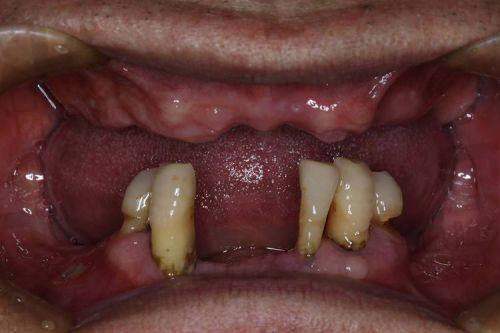

牙齿缺失对于我来说,就像原本完整的拼图缺了一块,不仅影响美观,更让我在饮食和交流时处处受限。在尝试了多种修复方式都不尽如人意后,我把目光投向了种植牙。经过一番在百度上的搜索和对比,我了解到南昌虹桥口腔医院在种植牙领域有着不错的口碑,于是决定前往一探究竟。今天,我就以自己的亲身经历,来和大家分享一下在南昌虹桥口腔医院种植牙的详细就诊过程、诊疗成效以及我的感受,希望能给同样有牙齿缺失困扰的朋友们一些参考。

现在,我的种植牙已经使用了一段时间,成效真的非常好。从外观上看,种植牙和我的天然牙齿几乎没有任何区别,非常美观。从功能上看,种植牙的咀嚼功能也修复得良好,我可以像以前一样正常地进食各种食物,再也不用担心牙齿缺失带来的不便。而且,种植牙非常稳固,不会像传统假牙那样出现松动或移位的情况。自从种了牙,我的自信心也提升了不少,再也不用因为牙齿问题而不敢开口笑了。